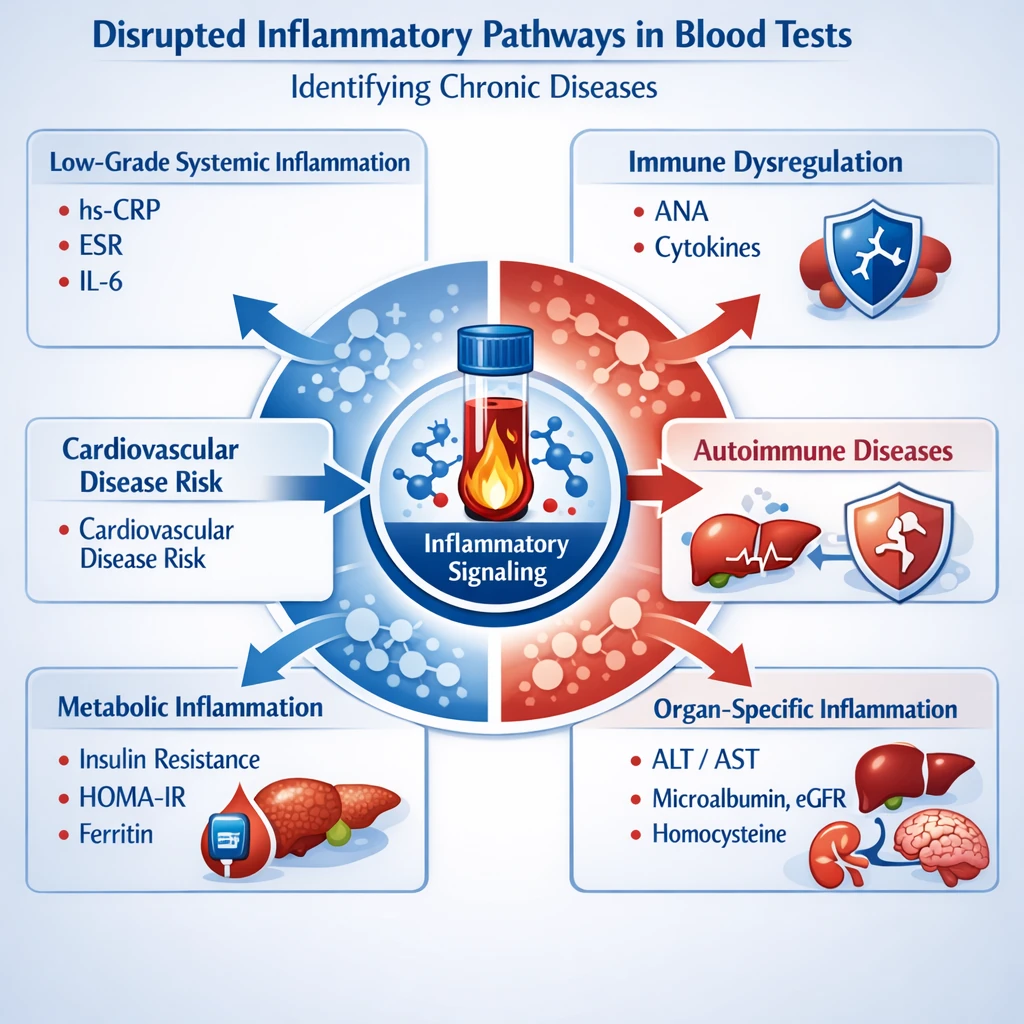

التهاب مزمن؛ عامل مشترک آسیب اندامها

یکی از مهمترین یافتههای آزمایشگاهی:

- افزایش hs-CRP

التهاب مزمن خفیف میتواند بهطور همزمان به قلب، کبد، کلیه و مغز آسیب برساند، بدون علائم واضح.